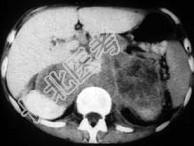

单项选择题男,76岁, 全身浅表淋巴结肿大,请结合下列图片作出诊断 ( )

A、肾上腺腺瘤

B、肾上腺癌

C、肾上腺嗜铬细胞瘤

D、肾上腺转移瘤

E、肾上腺淋巴瘤